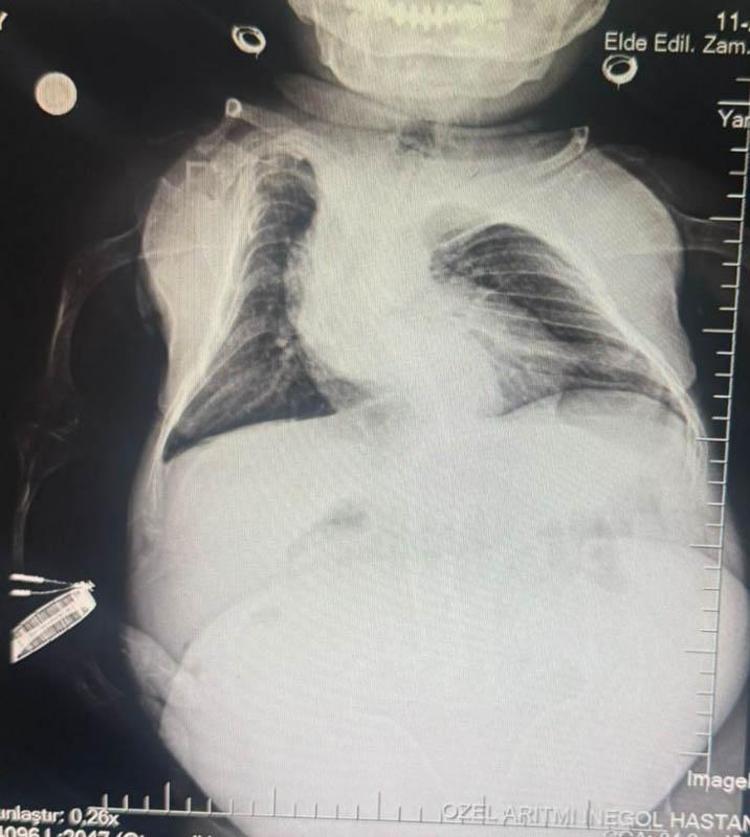

Halk arasında 'cücelik' olarak bilinen Akondroplazi rahatsızlığı ile dünyaya gelen Nurdan Tüfekçi, yaklaşık 1 yıldır karın ağrısı çekmeye başladı. Birçok kez hastaneye başvuran Tüfekçi, gördüğü geçici tedavilerin ardından taburcu olurken, şikayetleri artarak devam etti. İnegöl ilçesinde özel bir hastanenin kadın hastalıkları bölümüne başvuran Tüfekçi'nin yapılan tetkiklerde, yumurtalıklarında 3 kilogram kist olduğu tespit edildi. Epidural aneztezi ile 1,5 saat süren ameliyatın ardından yumurtalıklarındaki kist temizlenen ve sağlığına kavuşan Tüfekçi, ameliyat sonrası 21 kiloya düştü.

Kadın Hastalıkları Uzmanı Mustafa Kır, "Hastamızda 20 santimlik tümör vardı, kistlik yapıda. Onu başarılı bir operasyonla çıkarttık" derken, operasyonun başarılı geçtiğini söyleyen Anestezi Doktoru Mahmut Gül, operasyon sürecini şu sözlerle anlattı: "Hastamız, 30 yaşında, 80 santimetre boyunda, 24 kilo ağırlığında bir kardeşimiz.

Kendisinin yumurtalıklarında kist olduğu için ameliyat olması gerekti. Biz bu ameliyatta hastamıza önce büyük bir damar yolu açtık kasıktan. Çünkü damar yolunun çok önemi var ve daha sonrasında ameliyat sırasında belinden uyuşturduk ve ameliyatı sorunsuz bir şekilde, belden uyuşturmayla, hastamız uyanık bir şekilde tamamladık. Hastadan 3 kilo kist çıktı. Öncesinde 24 kilo olan hastamız ameliyat sonrasında 21 kilo ile şifalı bir şekilde serviste yatıyor. Başarılı bir operasyondu."